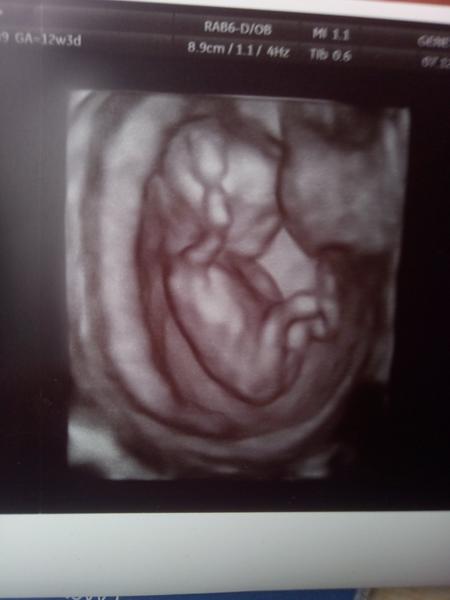

Kluk nebo jen pupeční šnůra?

Z ty tvoji fotky to neni jak poznat.. Jinak ve 12 tydnu jeste dite nema pindu/frndu, ale pouze takovy pohlavni hrbolek. Zkuseny doktor dokaze poznat podle jeho sklonu, jestli to vypada na holku nebo kluka.

Mě to odvodili podle úhlu pohlavního hrbolku. A trefili se. Takže jestli ti řekli, ze spis kluk. Tak to tak bude.

Ve 13tt neni zadny pinda, jen pohlavni hrbolek, u obou pohlavi zatim stejny, jen ma jiny sklon. Da se to poznat pouze z profilu a na klasickem utz a jen na tech velmi kvalitnich a vetsina doktoru to ani spolehlive neumi. Takze ze tvych fotek nevyctes opravdu nic, nech se zatim prekvapit.